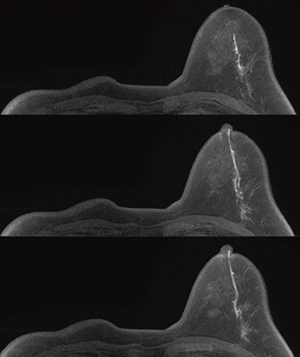

●安定した脂肪抑制が可能なEnhanced Fat Free法

2つの脂肪抑制パルスを用いた,新しい脂肪抑制技術であるEnhanced Fat Free法により,均一な脂肪抑制画像を得ることができます(図2)。

図2 片側切除の場合でも,信号強度ムラと脂肪抑制ムラがなく均一に描出